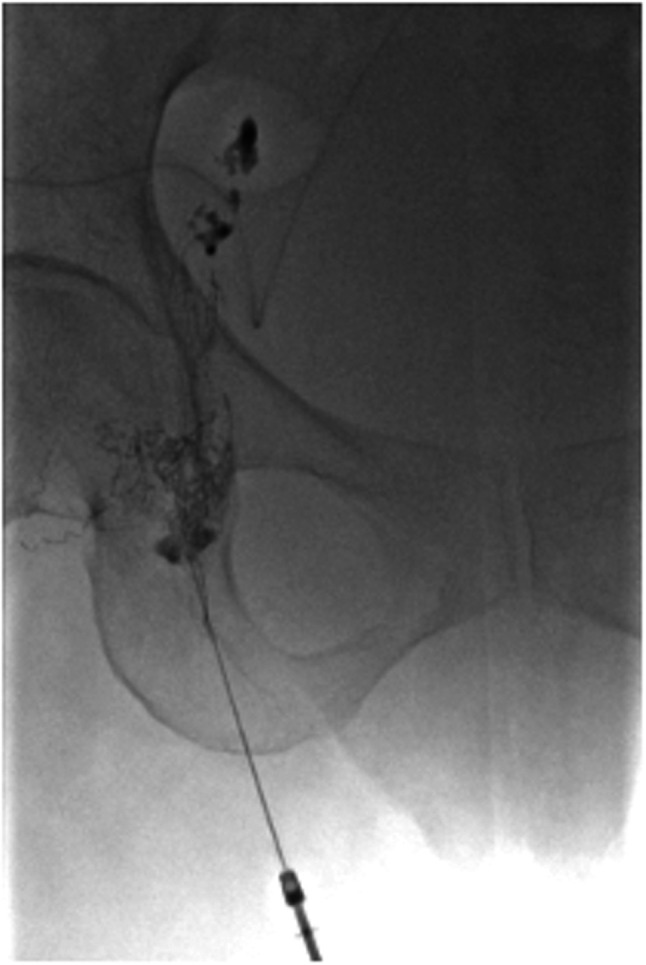

Case report: A 78-year-old woman underwent robotic-assisted abdominoperineal resection with right LLND for lower rectal cancer. She was discharged on postoperative day 12 but developed right lower abdominal pain on day 7 after discharge. Computed tomography revealed a fluid collection in the LLND area, diagnosed as a lymph cyst. Despite computed tomography-guided percutaneous drainage, the output remained high, and symptoms persisted. On hospital day 18, lymphangiography was performed using Lipiodol via right inguinal lymph node puncture. Within 3 days, the drainage output significantly decreased, and her symptoms improved.